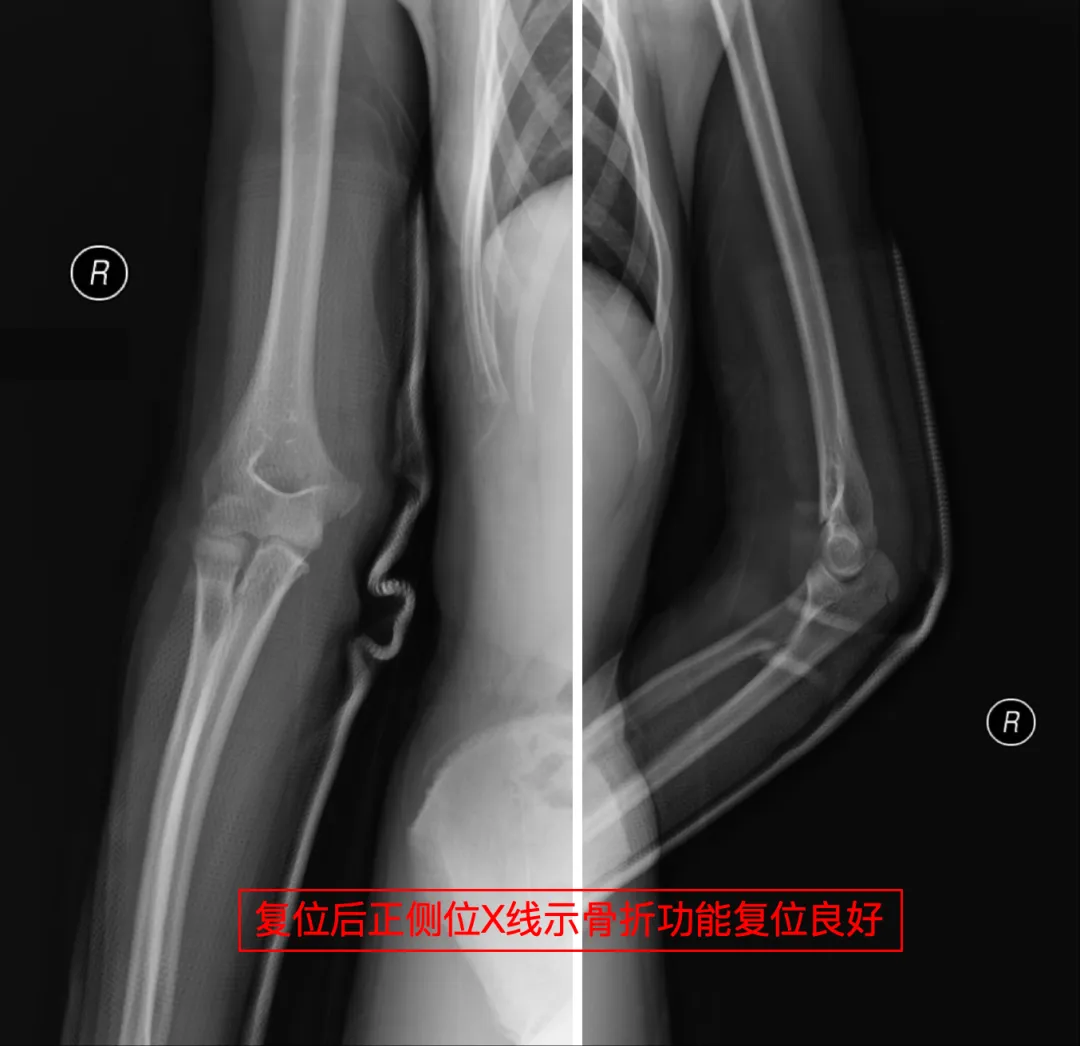

故事要从沙滩边的 “冲刺跑” 说起,菲菲本想和浪花比速度,结果脚下一滑,“咔嚓” 一声 —— 右肘(肱骨髁上骨折)疼得小姑娘当场飙泪,妈妈瞬间慌了神:陌生城市、孩子受伤、求医无门……脑子里全是问号。

急匆匆询问了一下本地人,她们来到威海卫人民医院手足外科就诊。拍片、诊断、复位、固定,整个迅速又专业的诊疗过程让李妈妈深感意外,主诊医生的精湛操作让孩子免于手术创伤,更令李女士动容的是无处不在的人文关怀医护人员耐心解答、细致指导,导医护士主动帮忙……最让李妈妈感动的是,接诊医生得知她们是外地游客,特意把复查时间安排得相对灵活。